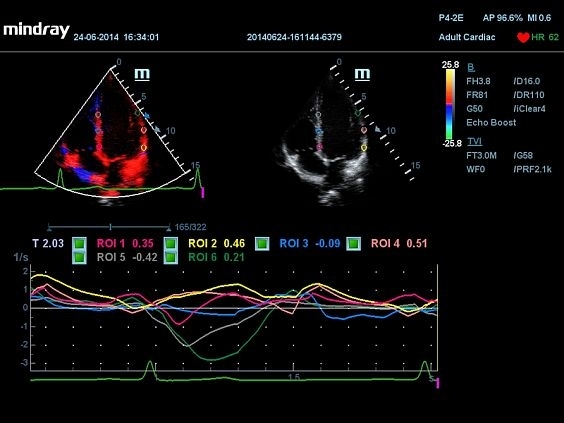

• TDI — тканевой допплер с цветным картированием, импульсным и энергетическим тканевым допплером и тканевым М-режимом;

• TDI QA — количественный анализ в режиме тканевого допплера (требуется опция TDI);

• Tissue tracking QA — недопплеровская количественная оценка движения и деформации миокарда (требуется модуль Physio Module для ЭКГ/ФКГ);

Изображения

Универсальные, Кардиологические, Гинекологические, Педиатрические, 3D/4D акушерство